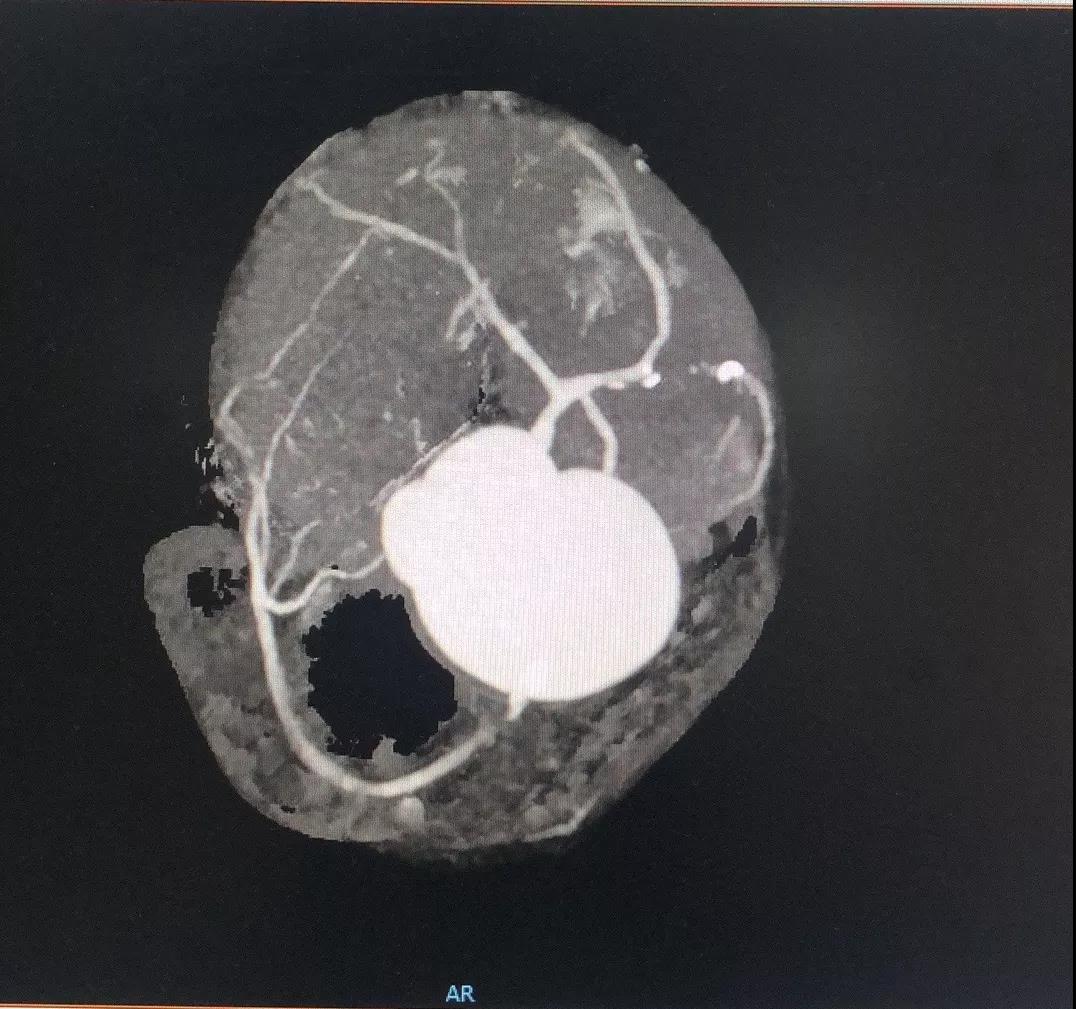

关于RCA

RCA CTA特点

1、入口清楚;

2、闭塞段长度小于20cm;

3、闭塞段血管无明显扭曲;

4、闭塞段内有两处明显的钙化斑块;

5、闭塞出口处血管相对比较“健康”;

6、侧枝血管汇入左室后支;

7、后三叉处的血管相对比较“健康”。